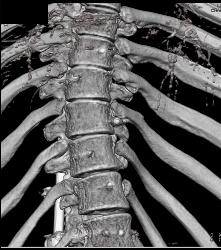

Small Caliber Aorta With Hardware Screw Abutting Aorta